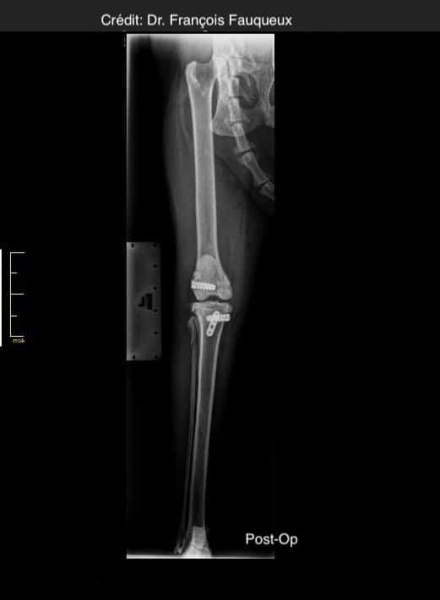

Radiologické snímky